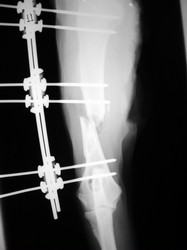

Fijación Externa

PRÁCTICAS CURSO DE FIJACIÓN EXTERNA PERFECCIONAMIENTO.

Húmero.